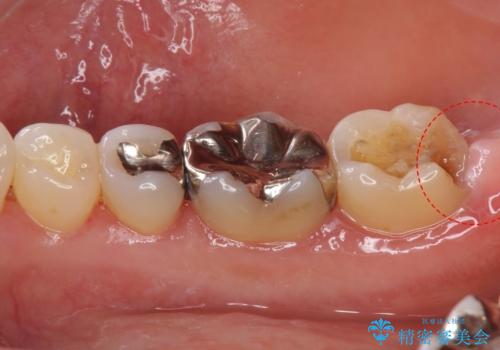

- 詰め物が外れたから作り直しをしたいとのことで来院されました。

外れた状態で日にちが経過していたため、まわりの歯ぐきが歯の上に乗っかっている状態です。

歯ぐきの形を整えてから治療をしていきます。